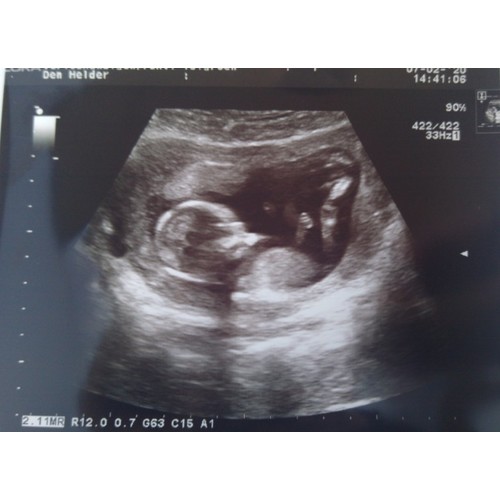

Wij hebben vrijdag de 20weken echo en dan hopen we ook te horen wat het wordt. Willen jullie alvast een gokje wagen om te zien of jullie gelijk zullen hebben? Dit was een echo van 16 weken